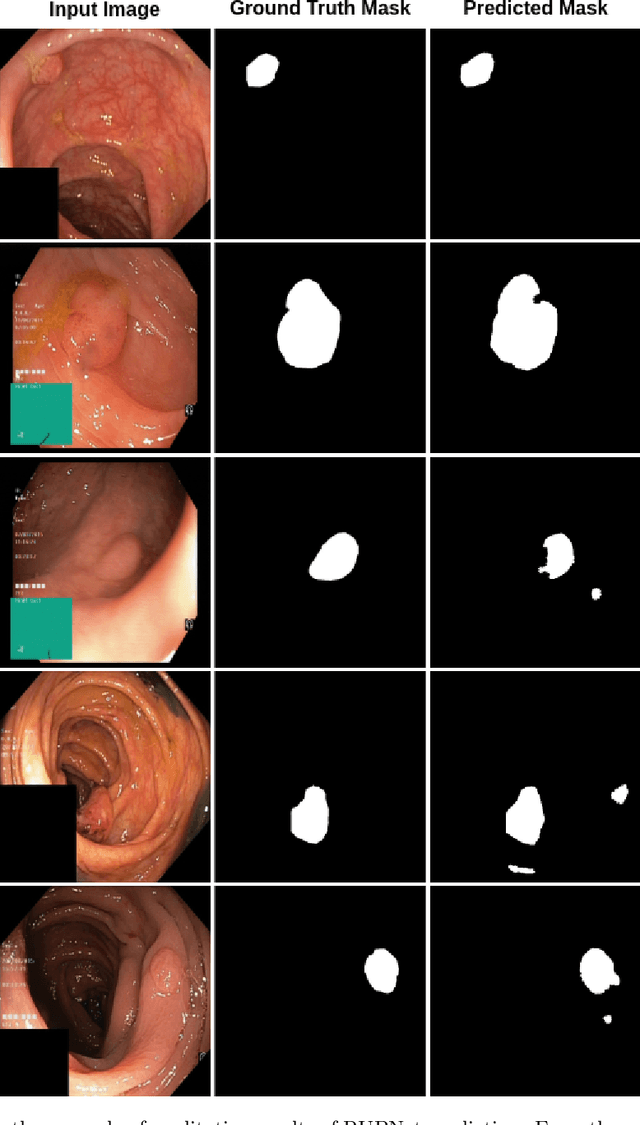

RUPNet: Residual upsampling network for real-time polyp segmentation

Jan 06, 2023

Colorectal cancer is among the most prevalent cause of cancer-related mortality worldwide. Detection and removal of polyps at an early stage can help reduce mortality and even help in spreading over adjacent organs. Early polyp detection could save the lives of millions of patients over the world as well as reduce the clinical burden. However, the detection polyp rate varies significantly among endoscopists. There is numerous deep learning-based method proposed, however, most of the studies improve accuracy. Here, we propose a novel architecture, Residual Upsampling Network (RUPNet) for colon polyp segmentation that can process in real-time and show high recall and precision. The proposed architecture, RUPNet, is an encoder-decoder network that consists of three encoders, three decoder blocks, and some additional upsampling blocks at the end of the network. With an image size of $512 \times 512$, the proposed method achieves an excellent real-time operation speed of 152.60 frames per second with an average dice coefficient of 0.7658, mean intersection of union of 0.6553, sensitivity of 0.8049, precision of 0.7995, and F2-score of 0.9361. The results suggest that RUPNet can give real-time feedback while retaining high accuracy indicating a good benchmark for early polyp detection.